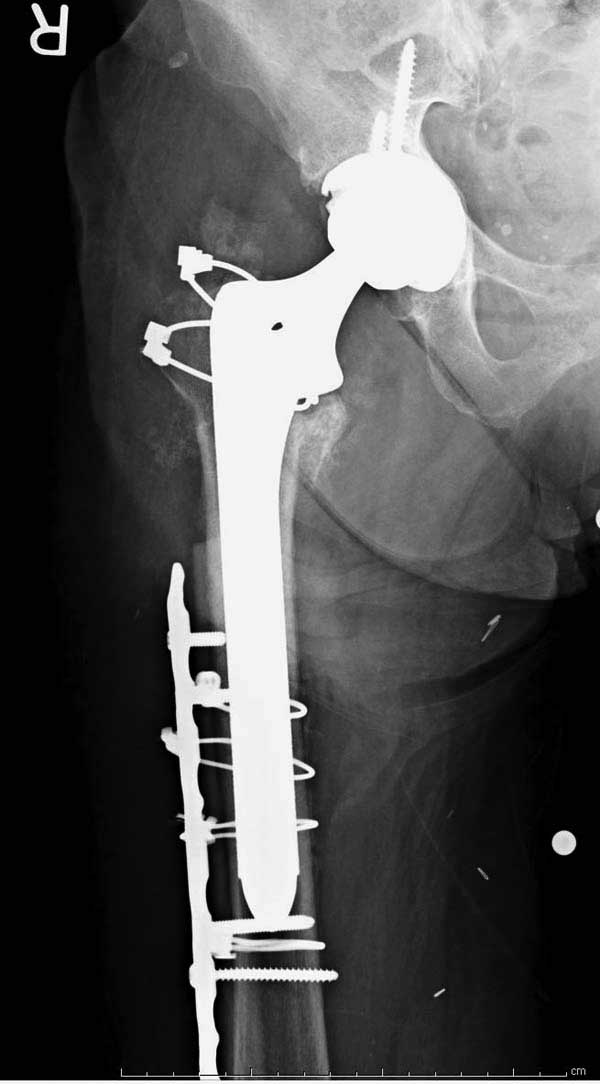

Третья операция-продолжения усилии "синьорами пэрами" по разрушению нормальной анатомии. Крест на головку! По видимому возраст позволяет биполярную конструкции, и при дефекте  calcar пошли на обычный цементный. Ягодичные мышцы потеряли связь с вертелом, т.е. отсутствует верхний удержатель, и результат “a Big Screw Up!” Снимки вызывают головокружение!

Если хирурги не устали от своих “творчеств”, тогда можно ре-оперировать с calcar replacement stem, и собрать остаток ягодичных мышц. Глубина и отстутствие артроза позволяет применить любой, биполярный или тотальный, хотя принять решение можно после ревизии ацетабулума.

Такие “чужие осложнения” встречаются у всех и представляю банальный случай, который шаг за шагом показано как перерос в более сложный процесс... Больная 70 лет, множественные ко-морбидности, чрезвертельный перелом первоначально фиксирован Гамма 3. Осложнение в течение 6 недель, ревизия тотальной артропластикой и во время установки ножки обнаружена трещина диафиза (17), из малого доступа фиксация алло-графтом.

Обычно после чрезвертельных переломов, за исключением молодых, у пожилых остается нестабильность при движении. Часто падают и после 3х мес. в результате падения обнаружен перипротезный перелом (22-23), который зафиксирован Синтез пластиной.